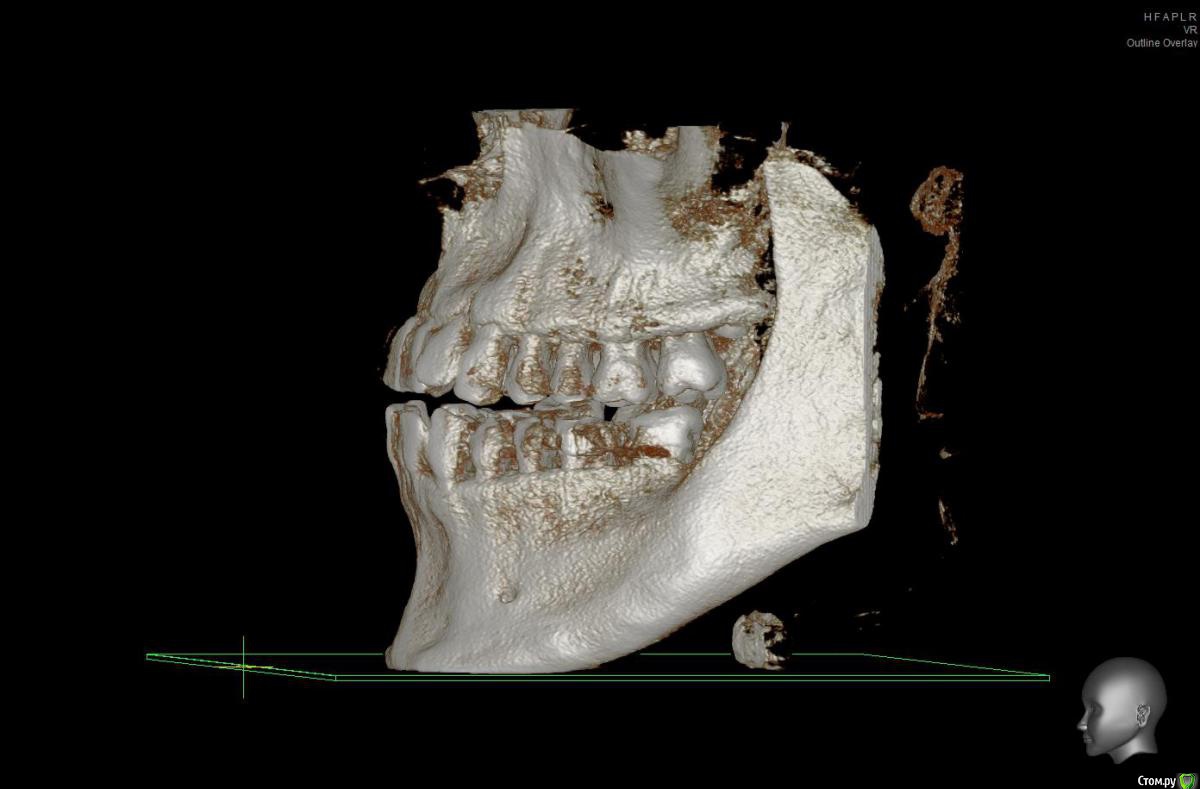

Brigita Опубликовано 3 апреля, 2017 Поделиться Опубликовано 3 апреля, 2017 Смысл невелик - Небольшое расширение на зубоальвеолярном уровне. Но проверить надо, есть ли куда расширятся- это можно на кт сделать. 1 Ссылка на комментарий

solitary Опубликовано 3 апреля, 2017 Автор Поделиться Опубликовано 3 апреля, 2017 Brigita, огромное вам спасибо, что находите время отвечать на мои вопросы http://i12.pixs.ru/storage/3/3/1/1jpg_6052132_25752331.jpgКТ у меня есть, сделанная в рентгенодиагностическом центре Пикассо. Если потребуется, я могу выслать. Сделал скриншот ВЧ, но наверное неправильно выставил оси в программе. Посмотрите пожалуйста. Ссылка на комментарий